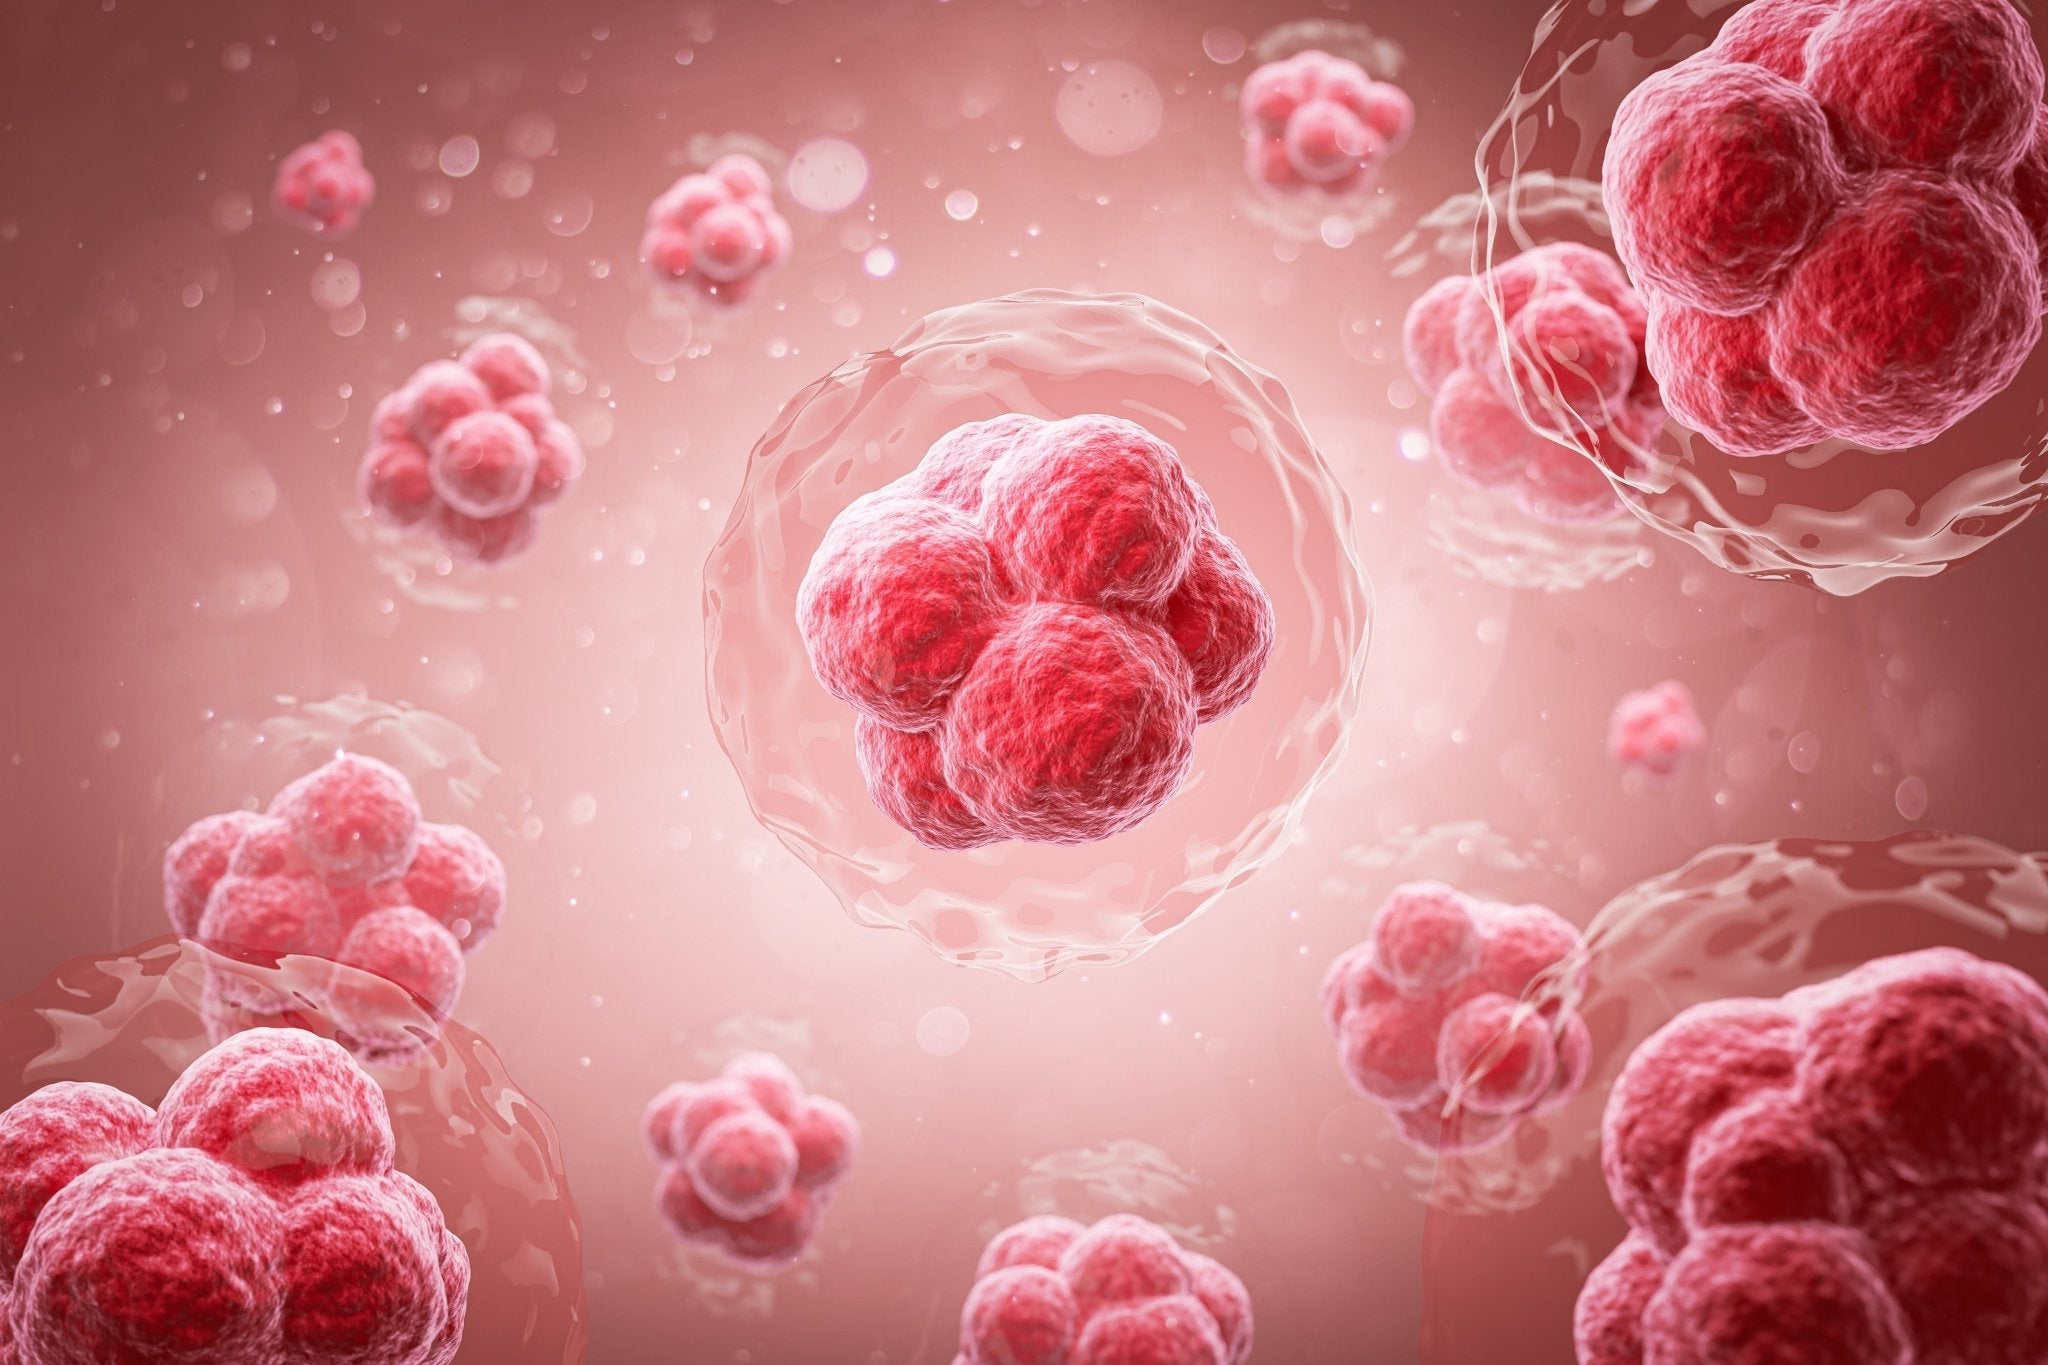

Red light therapy does not cause cancer and appears to...